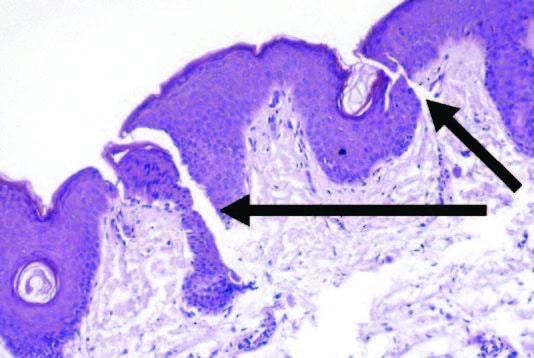

- This occurs at the dermal-epidermal junction (DEJ).

- This DEJ-shallow dermis area is the target depth to microneedle. See arrows where microchannels are formed

- This occurs at the dermal-epidermal junction (DEJ).

- This DEJ-shallow dermis area is the target depth to microneedle. See arrows where microchannels are formed

- Induce the activation, migration, and/or proliferation of melanocytes into hypopigmented areas at the dermal-epidermal(DEJ). This shallow dermis area is the target depth.

Microchannels provide space for melanocytes to migrate into non-pigment areas